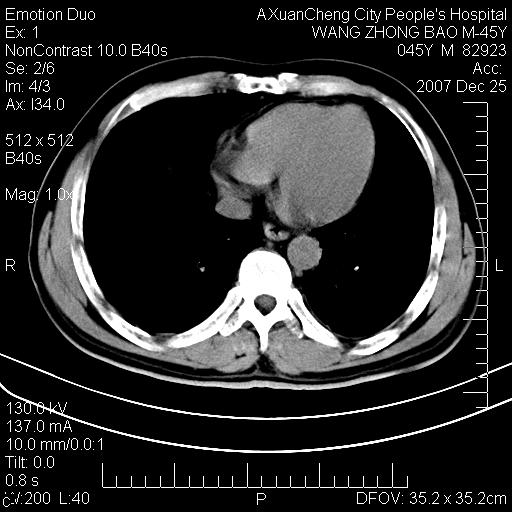

以下是引用qiuleiyu在2007-12-25 18:14:00的发言:[br]胰腺增大,周边渗出改变,肾前筋膜明显增厚,示少量积液.胆囊壁毛糙,周边少许渗出,胆总管壁厚,异常强化,然扩张不明显.结合病程急短;考虑;胆管炎,胆囊炎,胆源性胰腺炎可能大,请结合实验室检查及随访.

以下是引用lisihao在2007-12-25 14:23:00的发言:[br]急性水肿型胰腺炎[br]依据:1、胰腺弥漫性肿大,边缘稍毛糙;[br] 2、双侧肾周筋膜增厚,尤以左侧为甚(重要征象)[br] 3、双侧后胸膜增厚(刺激性炎症);[br] 4、结合病史,查血尿淀粉酶应该可以确诊。